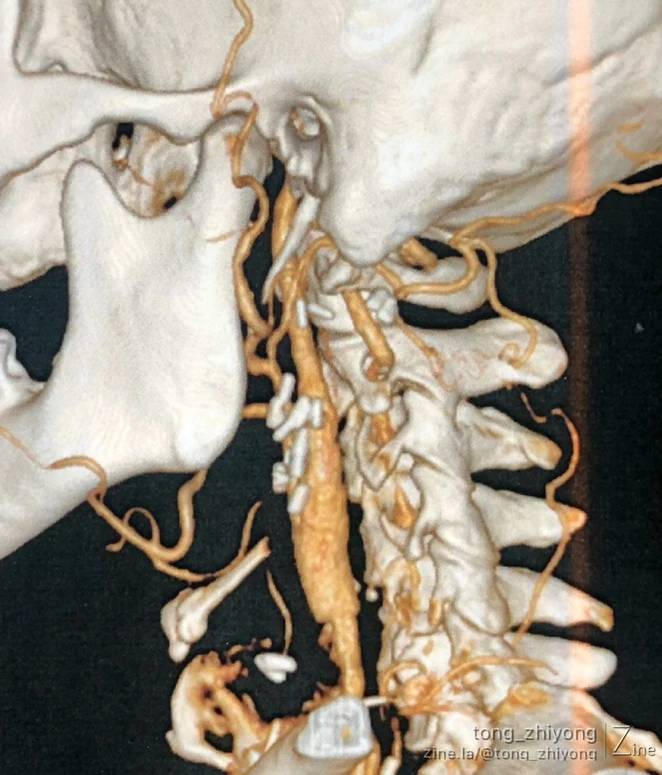

CTA确认:支架内重度再狭窄;

CTA确认:支架上端位于C2锥体上缘;颈内动脉内释放的6mm支架的直径“大于”远心端颈内动脉的直径。

显露到支架远心端颈内动脉,确认:颈内动脉内释放的6mm支架的直径“大于”远心端颈内动脉的直径。

术后一周CTA显示:颈部操作最上端到达C1锥体水平。钛结扎夹在CTA上像“香米粒”一样。

完全开通左侧颈动脉